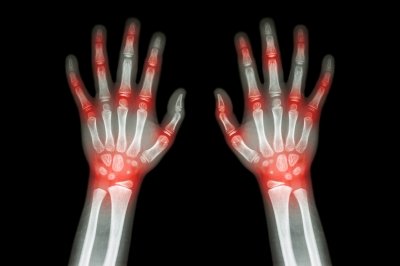

asam urat

5 Hal Krusial dalam Konseling Tentang Asam Urat Untuk Para Apoteker

Farmasetika.com – 6/6/2016. Banyak pasien yang menderita asam urat atau gout akan mencari bantuan ke klinik atau apotek terdekat untuk meredakan nyeri. Beberapa penelitian menunjukkan bahwa prevalensi penyakit ini terus meningkat.

Menurut survei WHO, Indonesia merupakan negara terbesar ke 4 didunia yang penduduknya menderita asam urat dan berdasarkan sumber dariBuletin Natural, di Indonesia penyakit asam urat 35% terjadi pada pria di bawah usia 34 tahun. Kadar asam urat normal pada pria berkisar 3,5-7mg/dl dan pada perempuan 2,6-6 mg/dl. Kadar asam urat di atas normal disebut Hiperurisemia.

Di sekitar setengah dari pasien, onset dimulai dengan jempol kaki yang parah dan meradang. Awal gejala juga dapat terjadi di pergelangan kaki, tumit, atau lutut. Kemudian dapat bergerak ke pergelangan tangan, jari, dan siku.

Gout disebabkan oleh hyperuricemia, gangguan metabolik yang tidak terkendali yang mengarah ke pengendapan kristal monosodium urat dalam jaringan sel sehingga terlalu banyak asam urat dalam darah. Asam urat adalah produk metabolisme yang dihasilkan dari metabolisme purin yang secara alami ditemukan dalam banyak makanan, seperti daging organ seperti hati dari sumber hewan dan beberapa jenis ikan, termasuk ikan teri, sarden, herring, dan ikan trout.